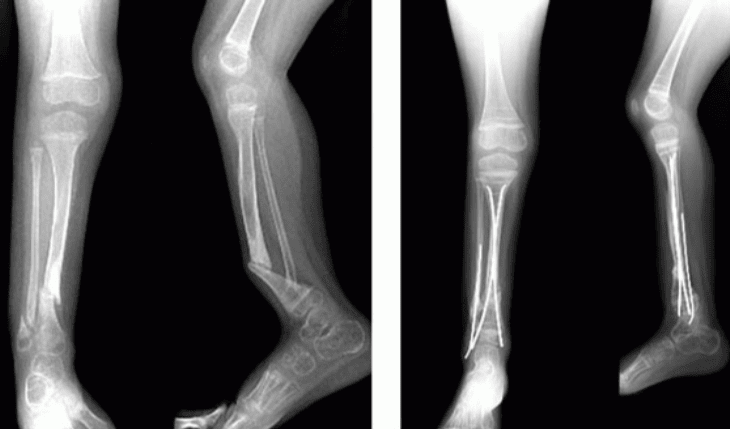

• Congenital pseudarthrosis of the tibia. Neurofibromatosis Type 1 can cause bones to grow abnormally. The tibia (shinbone) is the bone most commonly affected. In a small number of children with NF1, bowing of the tibia is one of the first signs of the disease, most often occurring before a child is 2 years old.

The tibia typically bows toward the front and to the outside of the leg (called an anterolateral bow). If the child has no other symptoms and has not yet been diagnosed with NF1, tibial bowing should prompt the pediatrician to fully evaluate the child for the disease. Although anterolateral bowing of the tibia may occur in patients without neurofibromatosis, it is associated with the disease 50% of the time (though only about 10% of NF1 patients develop this problem).

The bowing of the tibia makes it more vulnerable to a break, or fracture. Often, this fracture does not heal well due to the deformity of the bone, and may lead to a persistence of the fracture, known as a pseudarthrosis. Prevention of this sort of break is very important, as a pseudarthrosis of the tibia is very difficult to treat and requires surgery.

Treatment for Pseudarthrosis of the Tibia

Children with NF1 who have tibial bowing require special braces that are intended to protect the bone from fracture. If the bone breaks, surgery is frequently required.

During the operation, the bone fragments are first repositioned (reduced) into the best alignment possible, then held together with special implants.

These fractures, often delayed in their healing and referred to as pseudarthroses, are difficult to treat, and the surgeon may need to apply special bone grafts to stimulate healing. Refracture is common. If the bone does not heal despite several surgical interventions, the surgeon, patient, and patient's family may need to consider amputation.

Newer techniques now available utilize implants that allow for growth, better support, and extensive bone grafting, which can enhance healing.